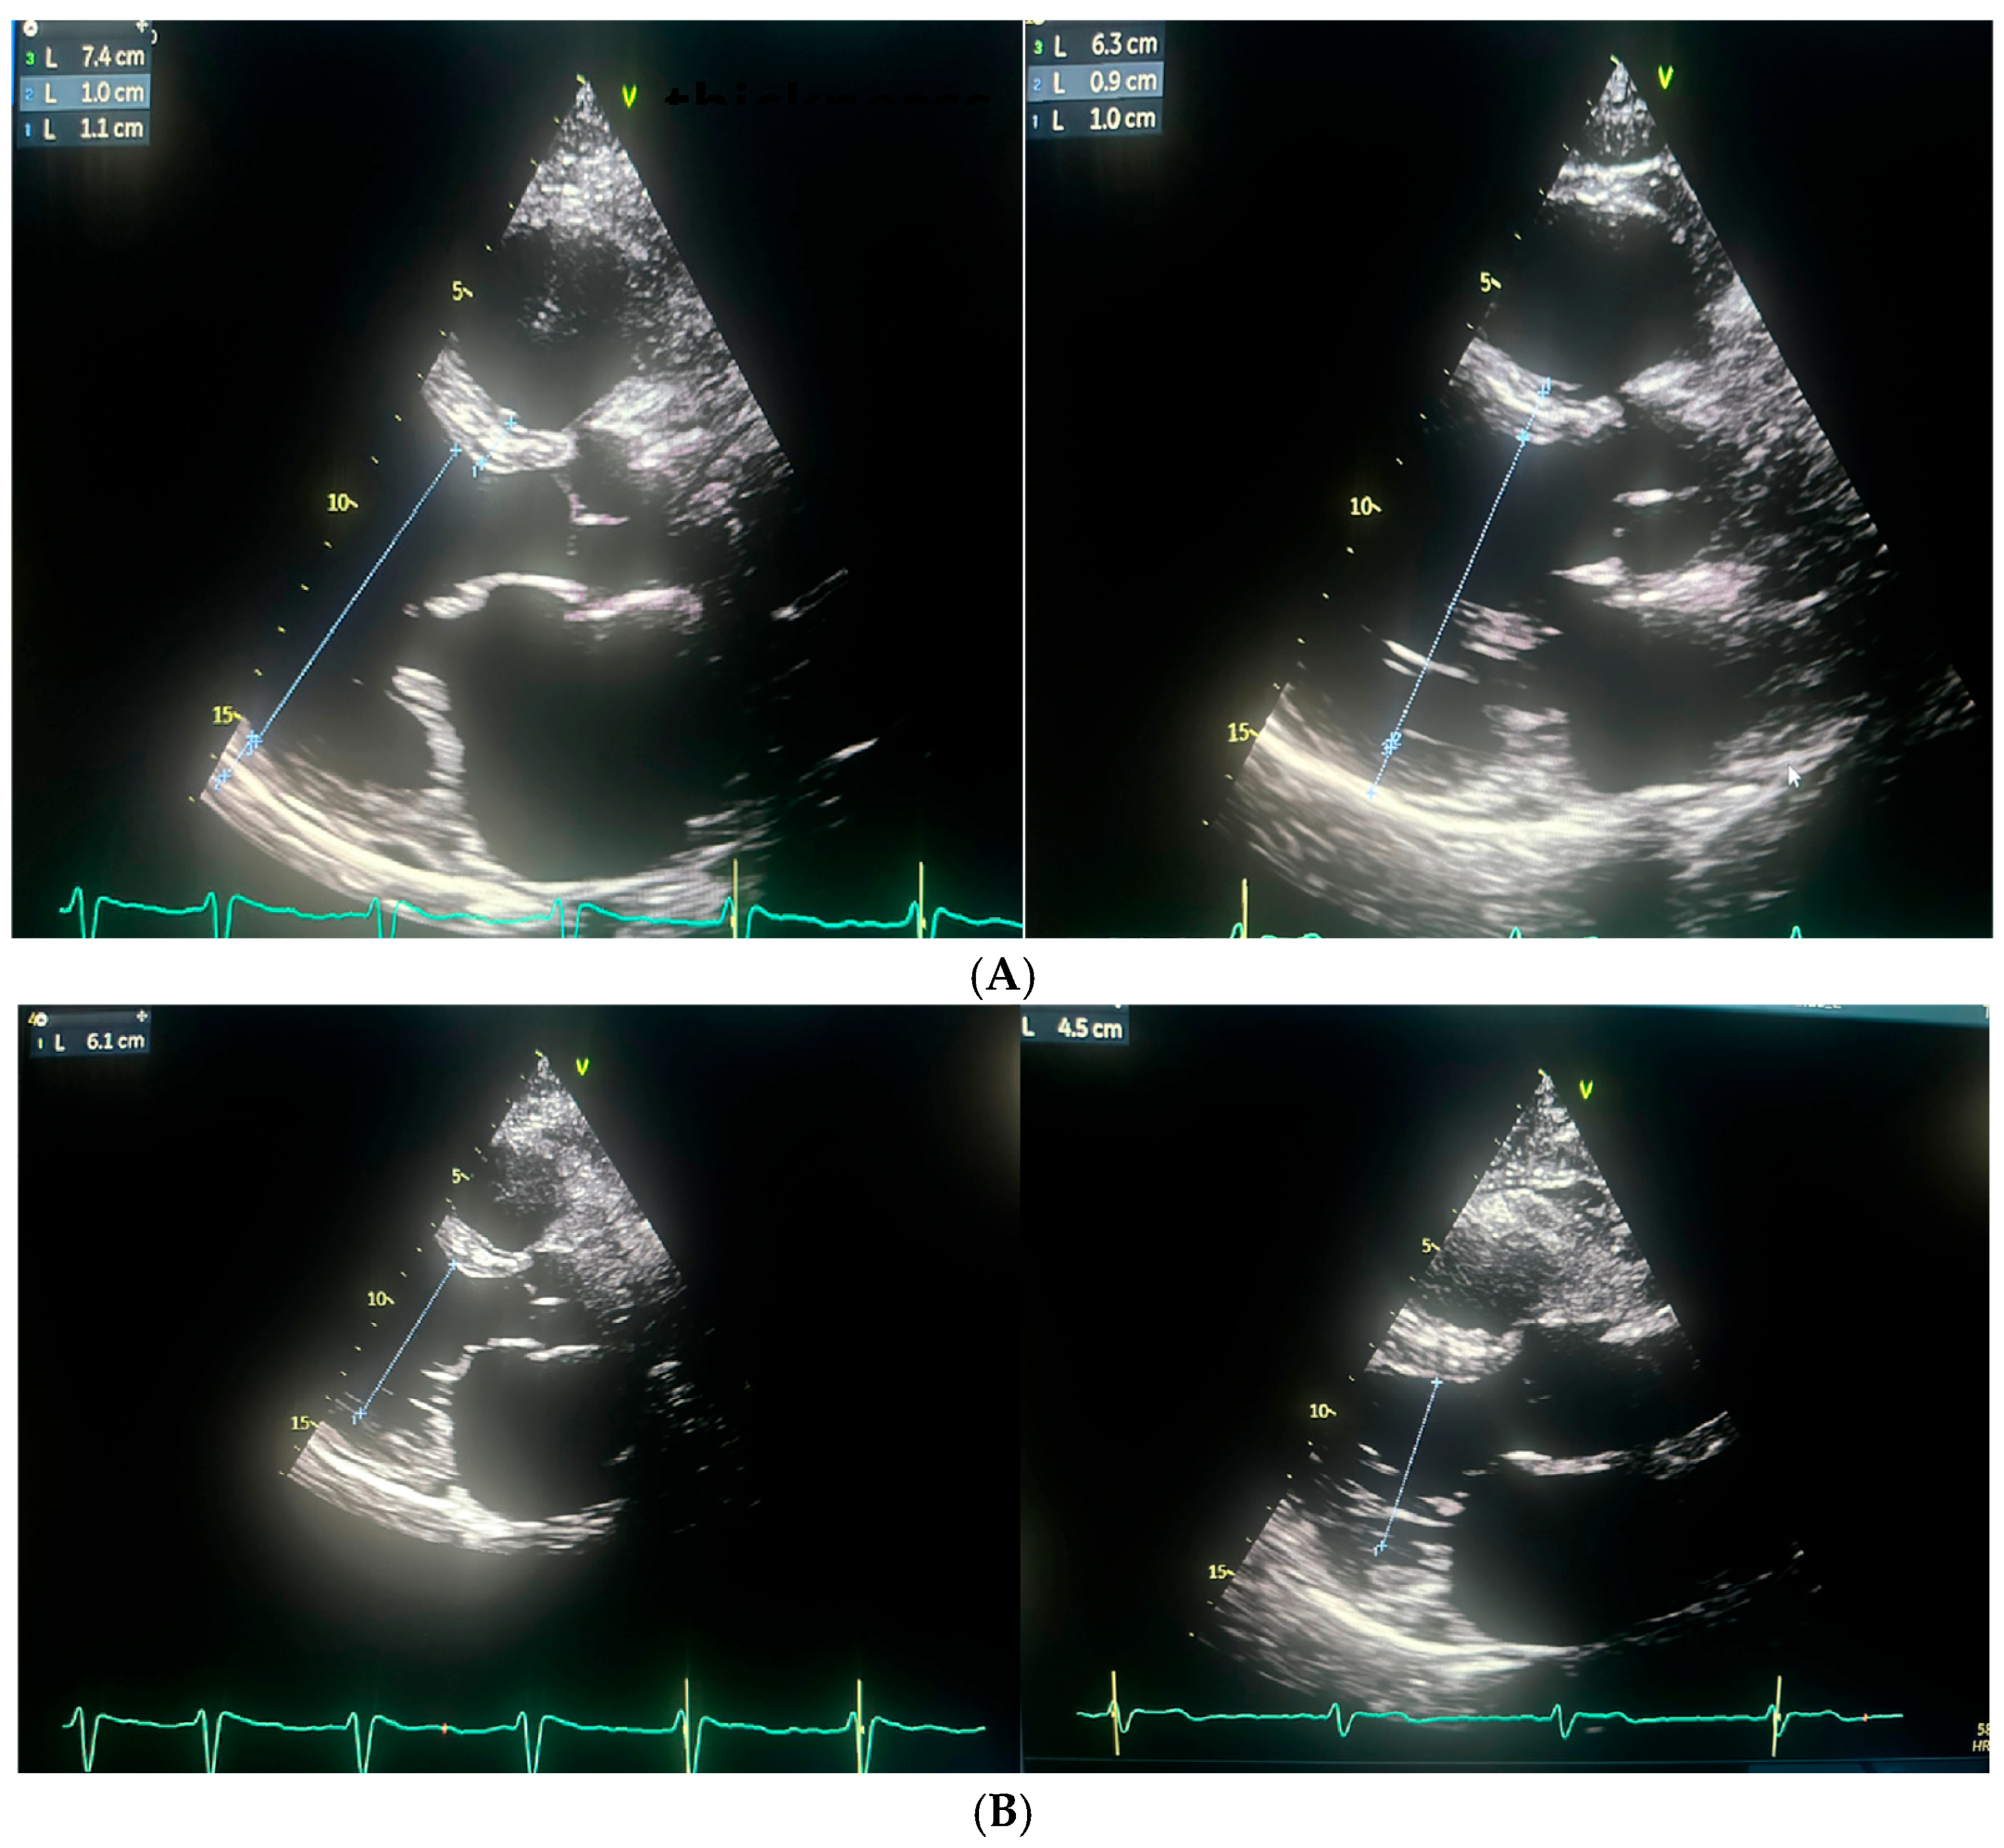

Repeated TTE demonstrated a slight improvement in left ventricular systolic function, with an LVEF of 25%. (Figure 3 and Figure 4).

Following the ablation procedure, chronic amiodarone therapy was discontinued. The patient was subsequently scheduled for follow-up visits approximately 2 months and 14 months after the intervention. Since the ablation, the patient remained in very good general condition, with no documented recurrences of arrhythmia, either symptomatically or on 24 h Holter ECG monitoring. There were no hospitalizations for arrhythmia-related events during this period. At the 14-month follow-up, TTE was performed and complete normalization of left ventricular systolic function was observed, with an LVEF of 55% (Figure 3 and Figure 4). Additionally, a reduction in the dimensions of both atria, the right and left ventricles, was noted. The previously elevated natriuretic peptide levels had also regressed significantly. Importantly, the patient’s functional status and quality of life improved markedly, as assessed by the ASTA questionnaire, with a score reduction from 24 points before the procedure to 0 points after ablation. General and echocardiographic parameters before and after ablation are presented in Table 2, Table 3 and Table 4 respectively.

Figure 3. The figure illustrates the changes in cardiac chamber dimensions as assessed by echocardiography, comparing measurements obtained before and after the ablation procedure. Echocardiographic parameters prior to ablation are displayed on the left, while post-ablation values are shown on the right. (A) Left Ventricle End Diastolic Volume (LVEDD) and myocardium; (B) Left Ventricle End Systolic Volume (LVESD); (C) Left atrium postero-lateral diameter; (D) Left atrium volume index (LAVI).